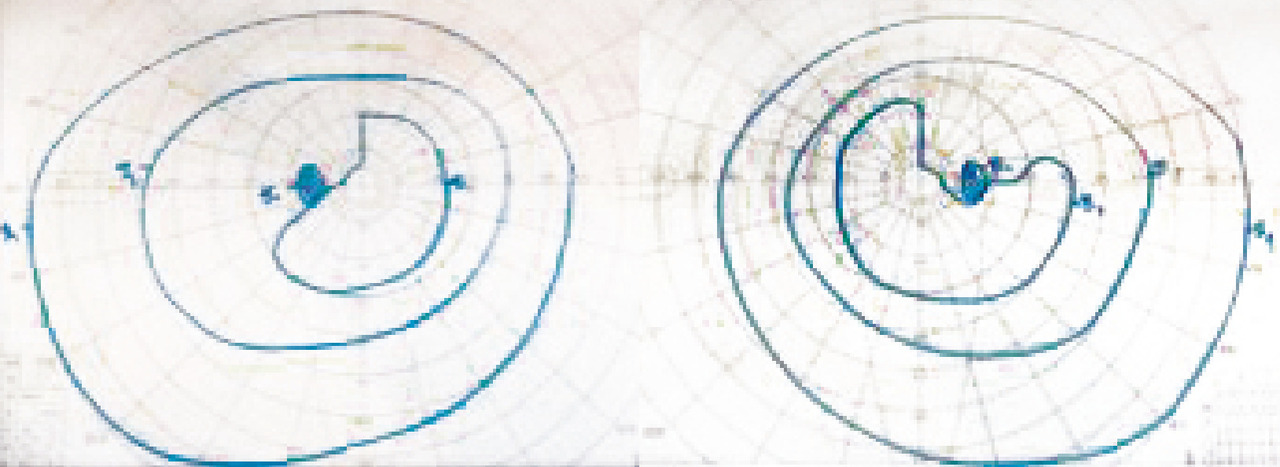

Anomalies du champ visuel

Les atteintes du champ visuel sont souvent difficiles à caractériser sans examen complémentaire, d’autant plus lorsqu’elles sont bilatérales. L’interrogatoire et la réalisation d’un champ visuel au doigt en cachant un œil ou sur une feuille de papier en dessinant ce qui manque permet de s’orienter lorsque la réalisation d’un champ visuel standard n’est pas possible en urgence (fig. 1).

Atteinte bilatérale : principalement chiasma et en arrière du chiasma

Dans l’atteinte chiasmatique ou rétrochiasmatique, on observe une atteinte bilatérale avec respect du méridien vertical. Au niveau du chiasma, l’hémianopsie est bitemporale, alors qu’en arrière du chiasma une lésion unilatérale donne une hémi- ou quadranopsie latérale homonyme controlatérale à la lésion.

Atteinte du chiasma optique

Le syndrome chiasmatique donne classiquement une quadranopsie bitemporale supérieure évoluant vers une hémianopsie bitemporale. Les causes sont dominées par les tumeurs hypophysaires, dont l’adénome hypophysaire et plus rarement le craniopharyngiome ou un méningiome (fig. 3).

Le diagnostic est évoqué devant une hémianopsie latérale homonyme, controlatérale à la lésion. Les atteintes sont rares et les causes sont vasculaires en cas d’accident vasculaire cérébral (AVC) [début brutal], tumorales (début progressif) ou traumatiques.

Atteintes des radiations optiques

Elles entraînent une quadranopsie (voire hémianopsie) latérale homonyme et opposée à la lésion. Par exemple, une atteinte de la radiation inférieure (temporale) droite est responsable d’une quadranopsie supérieure gauche et une atteinte supérieure (pariétale) d’une quadranopsie inférieure controlatérale. Les causes sont les mêmes que dans le cadre des atteintes des bandelettes optiques (fig. 4).

Atteinte du cortex visuel

Les atteintes occipitales sont responsables d’hémianopsie latérale homonyme « à couper au couteau » controlatérale à la lésion (fig. 5). Dans le cas d’une atteinte bilatérale (AVC du tronc basilaire), l’atteinte peut aller jusqu’à la cécité corticale. Les patients ont classiquement une conservation du réflexe photomoteur et une anosognosie, rendant le diagnostic difficile. Les causes sont les mêmes que celles des atteintes des bandelettes et des radiations optiques avec, en cas d’atteinte bilatérale, des causes toxiques, comme l’intoxication au monoxyde de carbone (CO).